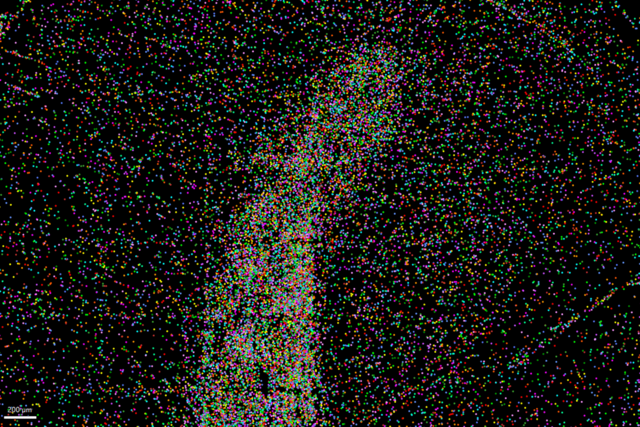

LAS X Navigator使用によるH&E染色した組織のタイリング画像 AI画像解析ソフトウェアAiviaによるターゲット細胞タイプのセグメンテーション

LAS X Navigatorでタイリング画像を作成し、Aivia画像解析ソフトウェアで画像のセグメンテーションを実行する。